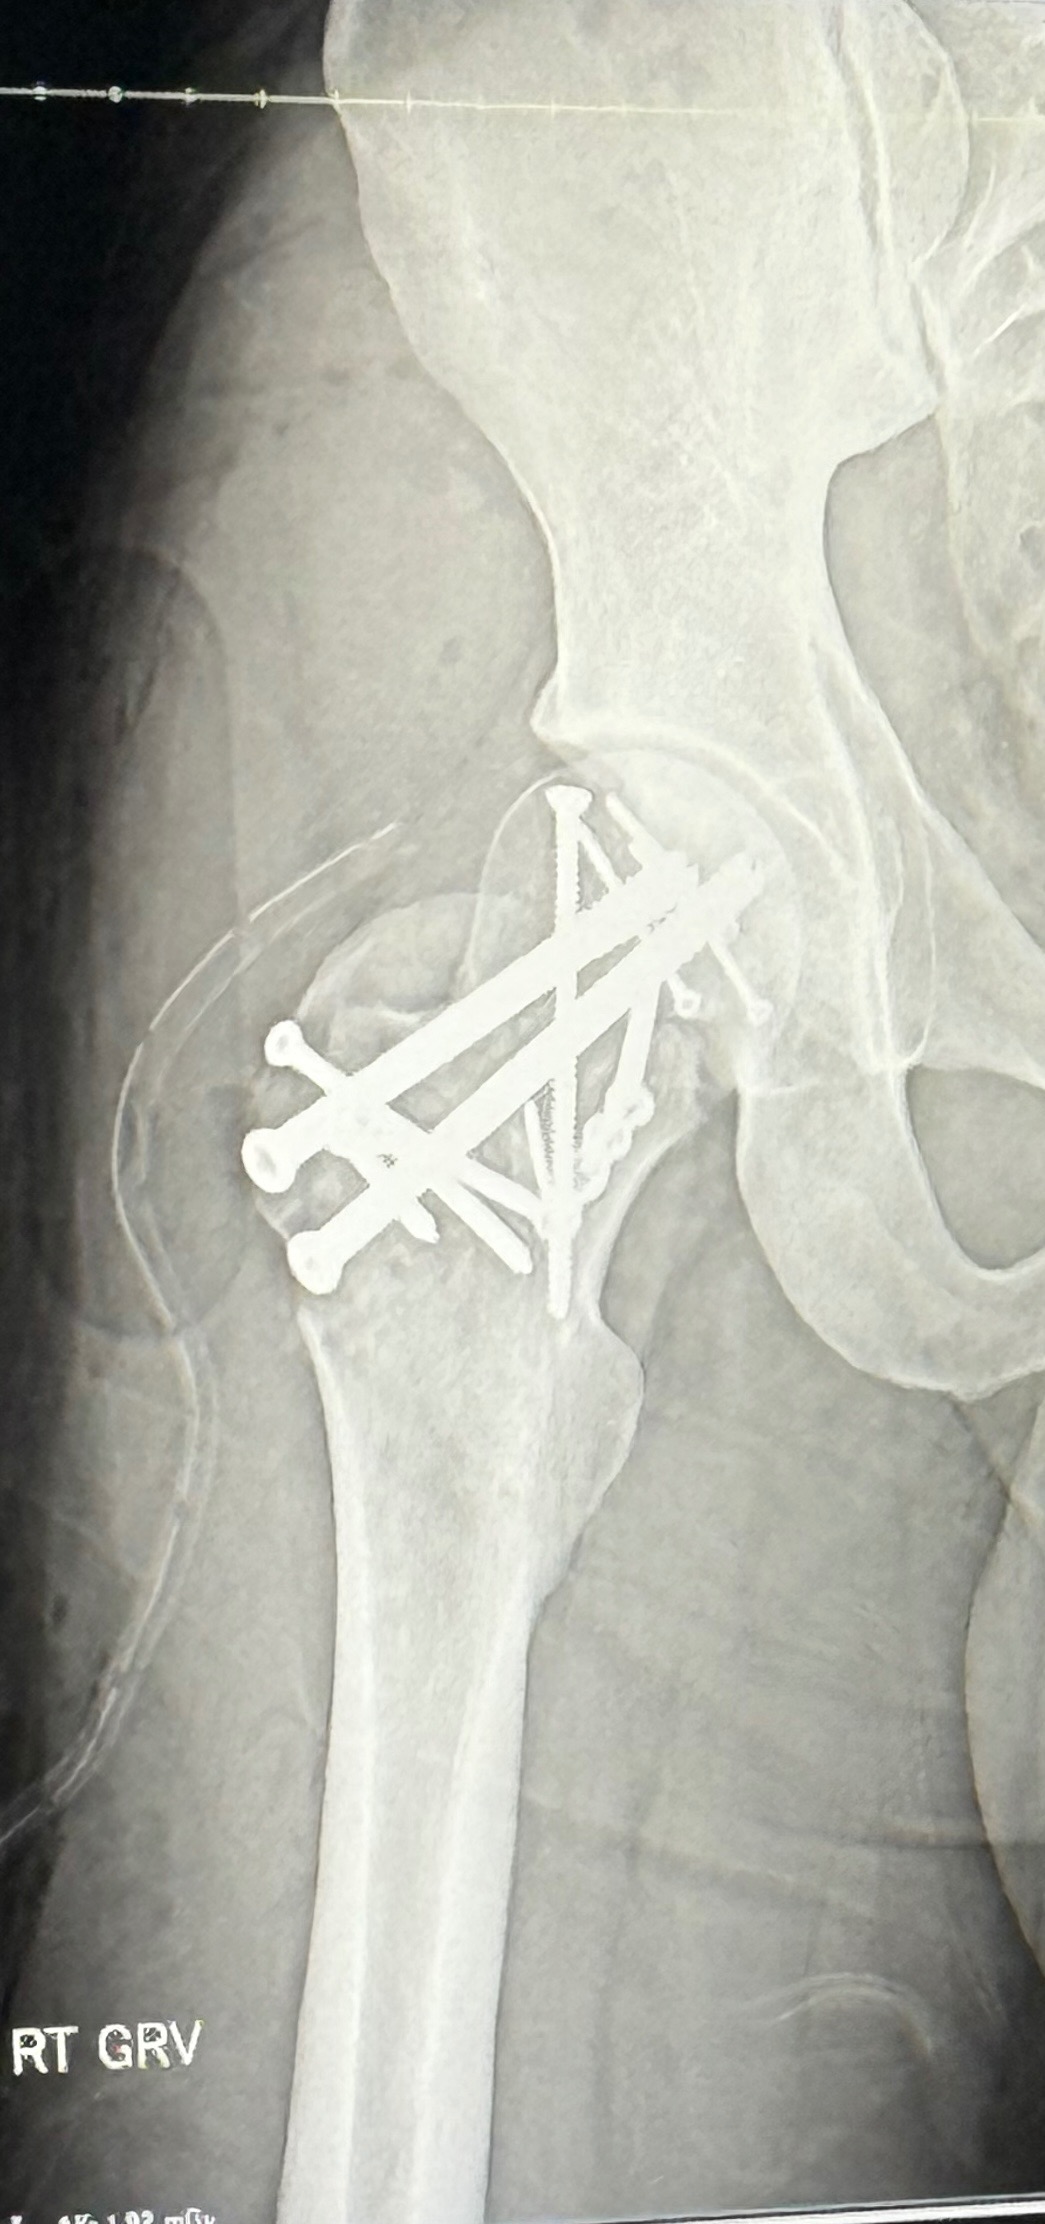

During a baseball game in mid November, Caden's world (and mine) was turned upside down. As he stepped off 3rd base, his right hip dislocated. At the small ER he went to, as the doctor tried to set the hip back into place, the femoral neck and head broke in half, causing major damage. He was then rushed by ambulance to a level 1 trauma center for emergency surgery. What was a normal evening until then, quickly turned into a nightmare, as he's being prepped for surgery, I was rushing from 5 hours away to get to him. I was not prepared for the aftermath.

Due to the severity of his injury, he underwent a lengthy surgery to try and save his hip, and he emerged with a steel plate and 13 screws. His surgeon said it was "complex and incredibly complicated" and "he did the best work he could". We spent over a week in the hospital (10/10 don't recommend) and then had to pack up some things and he has had to move from Texas to Oklahoma to live with me temporarily, since he can't walk, drive, work, etc. This too has added to his stress, as he is severely homebound and largely immobile. All of that to say, Caden is looking at ongoing medical care, more surgeries (there is no guarantee that the surgery will hold, and we could be looking at a total hip replacement in the next few months), physical therapy, and a long recovery period that will keep him completely non weight bearing until end of February.